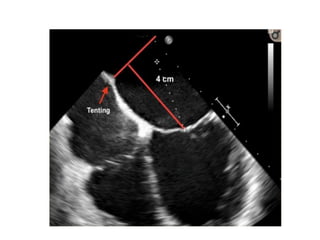

Transseptal puncture

• Optimal puncture site is superiorly and posteriorly in the interatrial

septum

• 3D TEE planes are used to determine the correct site

• Position of the BRK transseptal can be seen by a tent-like indentation of

the interatrial septum (‘tenting’).

• The site of optimal transseptal puncture is different for degenerative and

functional MR.

• In degenerative disease (e. g. prolapse), the puncture site needs to be 4–

5 cm above the mitral annulus to give enough space for adequate catheter

and MitraClip maneuvering.

• In contrast, in cases of functional MR, the line of coaptation is usually

below the plane of the mitral annulus due to extensive tethering.

• Therefore, the puncture site in these patients needs to be more inferior

and closer to the annular plane (about 3.5 cm above the annular plane).

Transseptal puncture • Optimalpuncture site is superiorly and posteriorly in the interatrial septum • 3D TEE planes are used to determine the correct site • Position of the BRK transseptal can be seen by a tent-like indentation of the interatrial septum (‘tenting’). • The site of optimal transseptal puncture is different for degenerative and functional MR. • In degenerative disease (e. g. prolapse), the puncture site needs to be 4– 5 cm above the mitral annulus to give enough space for adequate catheter and MitraClip maneuvering. • In contrast, in cases of functional MR, the line of coaptation is usually below the plane of the mitral annulus due to extensive tethering. • Therefore, the puncture site in these patients needs to be more inferior and closer to the annular plane (about 3.5 cm above the annular plane).

• #22 The puncture site is evaluated using TEE in a 4-chamber view, and the ‘tenting’ of the atrial septum can be seen as the transseptal needle is pushed against it, ideally in the superior and posterior part of the interatrial septum with the aim of obtaining adequate working space and distance above the mitral annulus